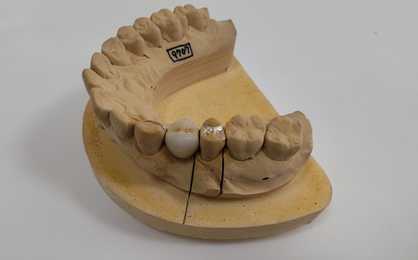

症例⑩

50代女性、左上5番を失ってしまい、他院でブリッジかインプラントをすすめられたそうです。しかしながら歯を大きく削るブリッジに抵抗があり、インプラントも「手術までしなくても・・・」という気持ちがあり、悩んでおられた時にヒューマンブリッジの存在を知り、当院に相談に来られました。※撮影技術が未熟なため模型上の写真でご紹介します。

●セット前の様子(頬側から)

●左上4番のパーツをセットしたところ

●左上6番のパーツをセットしたところ

●ポンティックをセットしたところ